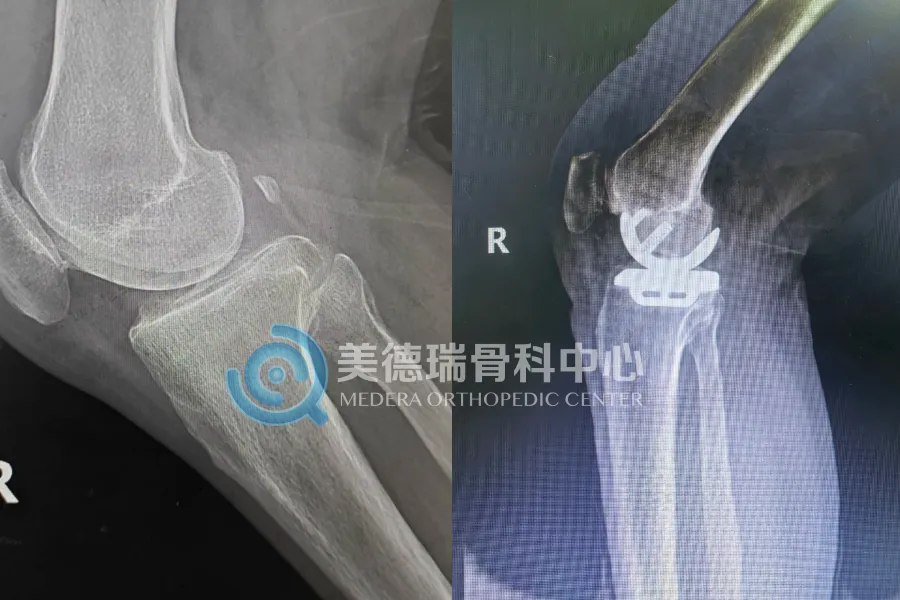

75岁的贾先生,膝关节退变局限于内侧间室,影像学显示其前交叉韧带功能完好,外侧及髌股关节软骨尚佳。对于这种“局限性”病变,团队并未采用传统的全膝关节置换,而是为他实施了单髁置换术(UKA)。这种术式只置换病损的内侧间室,保留了患者自身的韧带和正常的关节结构。